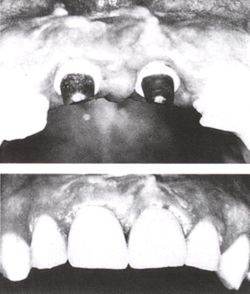

وفي الأسواق اليوم نماذج كثيرة من الزرعات التيتانية التي أصبحت الشكل الوحيد المقبول للتعويض عن فقدان الأسنان، وهناك تقنيات عدة لتثبيتها منها ما يعتمد على الغرس بطورين من الزمن؛ تبقى الزرعة في الطور الأول مطمورة في العظم ويثبت الجزء البارز من اللثة في الطور الثاني، ومنها ما يأخذ شكله النهائي مباشرة في عمل جراحي واحد. وتثبت الإحصاءات نجاح النمط الأول بنسبة أعلى من النمط الآخر.

تكون الغرسة مفردة أو متعددة أو شاملة، ويميز في طب الأسنان بين أربعة أنواع من الغرسات: التثبيت بالغرسة عبر السن transdental fixation والغرسة تحت الغشاء المخاطي submucosal implant والغرسة تحت السمحاق subperiosteal implant والغرسة في العظم enossal implant.

أما النوع الثالث، فأول من جربه مولّر عام 1937، إذ قام بزرع شبك معدني تحت السمحاق على طول الحافة السنخية للفك السفلي، مع بروز أربعة مهاميز خارج الغشاء المخاطي إلى جوف الفم لتحمل الجسر التعويضي. طوَّر دال الطريقة عام 1943 فصنع الشبكة من الكروم - كوبالت، غير أن عدم التطابق الكامل بين سطح الشبكة وسطح العظم الحامل لها يؤدي إلى خلل التوزع في الضغط، مما دعا الباحثين إلى كشف العظم وأخذ طبعة حقيقية لسطحه، والعودة إليه بعد صنع شبكة مطابقة له، وهذا يعني اللجوء إلى عمليتين لتحقيق الغاية بما في ذلك من رض.